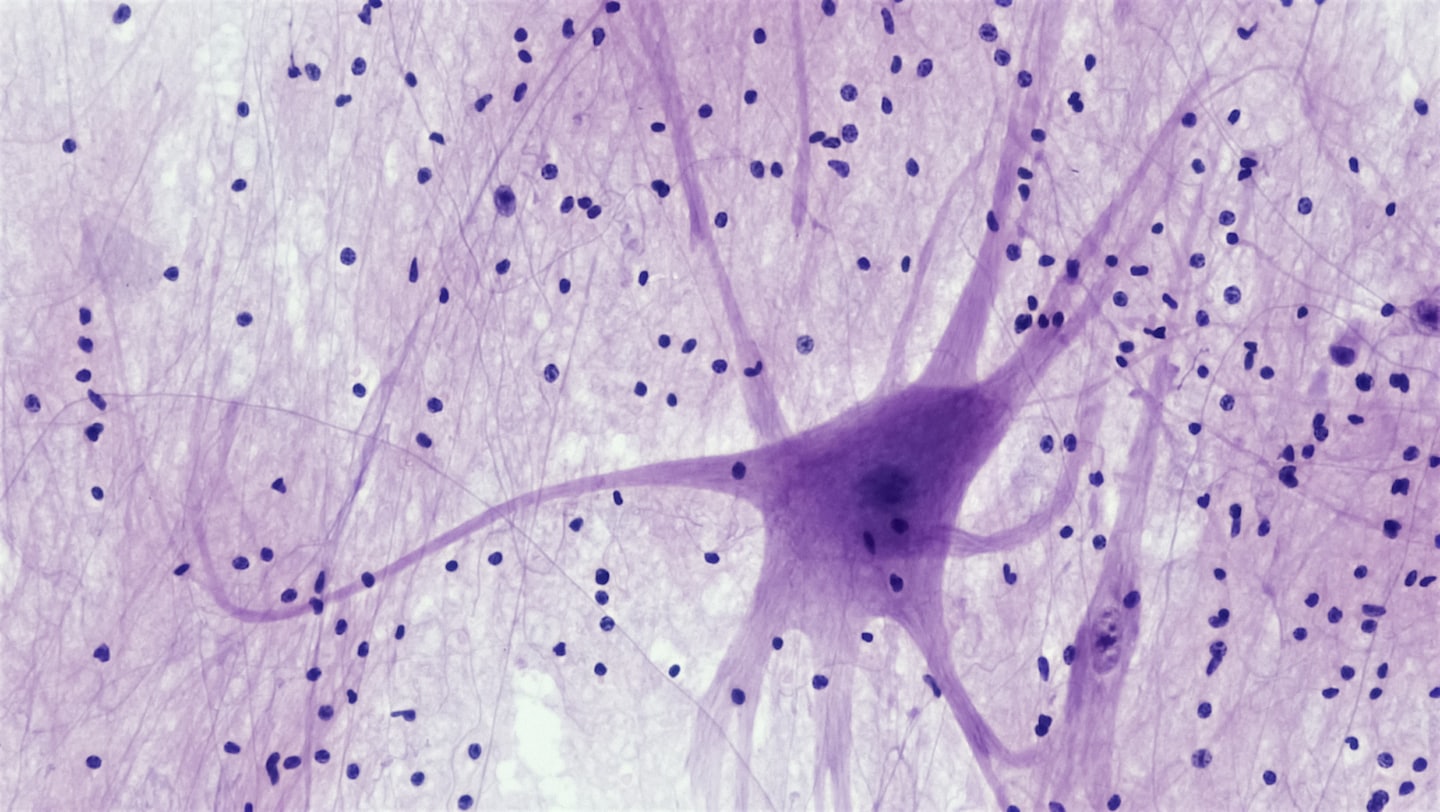

Neuroformación: excelencia en capacitación en Biotecnologia, Neurociancias y Neuroterapia

Aplique los ultimos avances en Neurociencias, Neurotecnologia y Neuroterapia en su consulta o negocio.